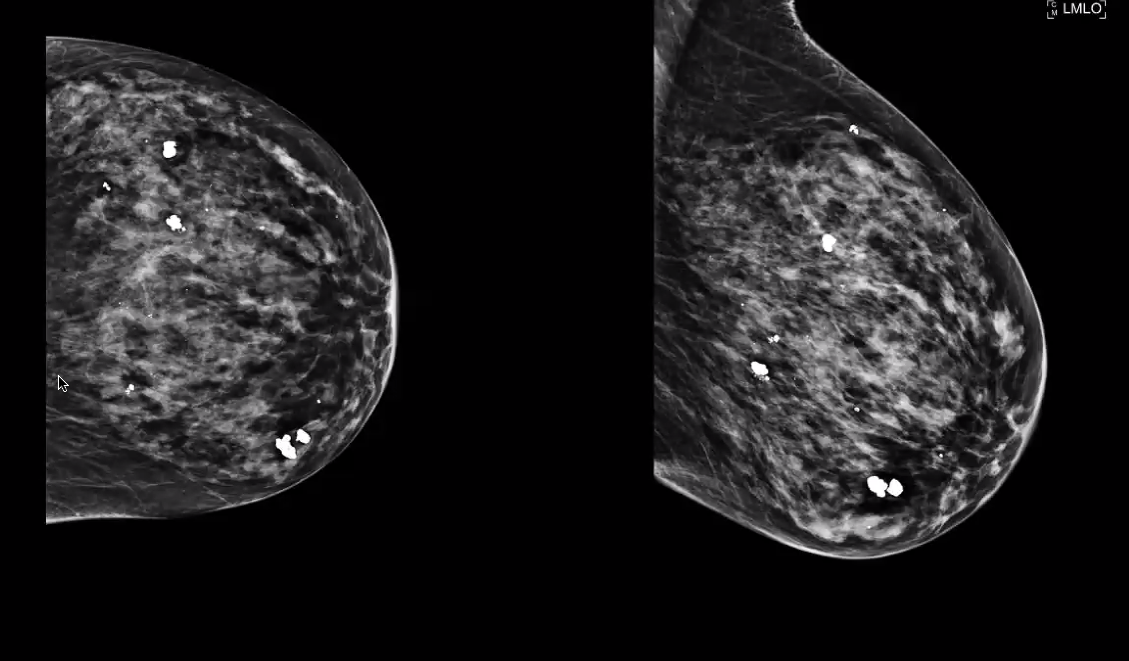

fine pleomorphic

= scary

BR 4 or 5

segmental fine pleomorphic calcs. BAD!

BR 5